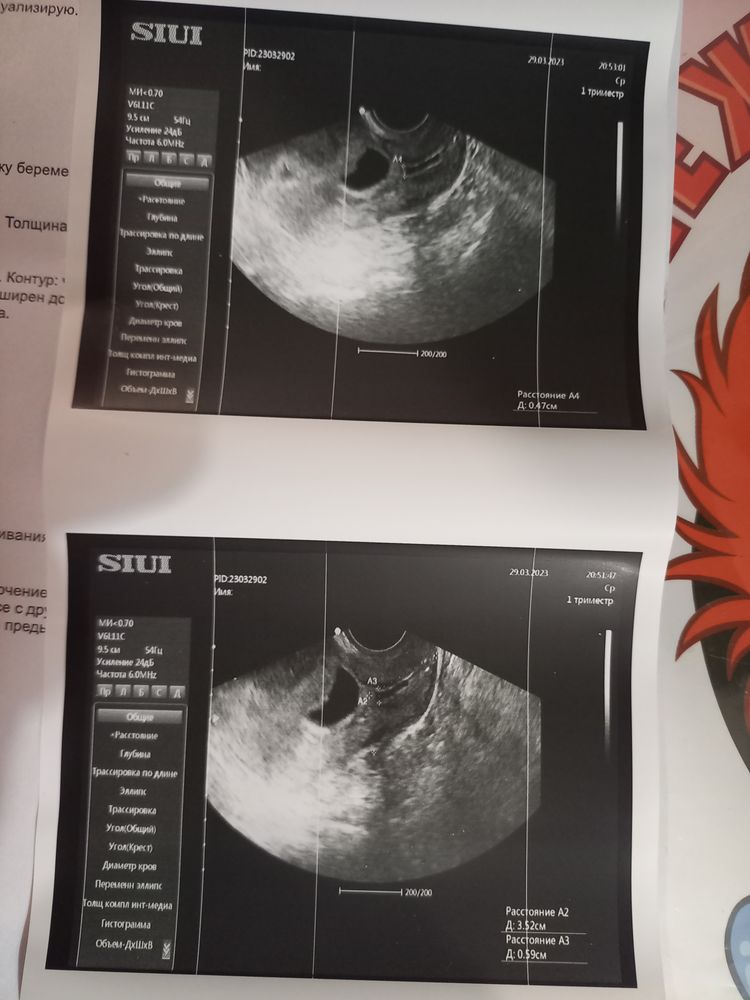

Снизу верно написала девушка, обычно либо пишут "сомкнутая часть длиной" или что-то подобное. Ни формы внутреннего зева, он внутри у Вас открыт или, может, все же снаружи. Непонятно. Раз написали "угроза", скорее внутри, то есть v-образный, что нехорошо. Но, он бывает от УЗИ к узи меняется, нет тонуса- закрылся. Но вообще ситуация не ахти, надо Вам к врачу побыстрее. Ещё вот форма пя меня смущает, из-за тонуса, видимо.

Наталья, ну если я правильно поняла, а я не врач, по 2,3 фото, не очень узи. Канал почти по всей шейке разомкнут. На месте где внутренний зев переходит в канал нет черноты, но я хз, если честно по этому поводу. У меня перед установкой пессария прям вот все в форме воронки было. Темнота на экране. Сохранять Вас надо.

Lena Fried, вот на этих снимках доктор показывала мне,все по отдельности:на одном-плодное яйцо деформированное,на другом-сердечко,на третьем-как раз вот это цервикальный канал.Короче,надо бежать к гинекологу срочно

Был тоже просвет по всему каналу но меньше. 1.6мм. Для повторнородящих это в порядке нормы считается. У вас есть реальная угроза. Гинеколог должен будет решить что делать и как вам помочь. Не напрасно вы переживайте. Тонус часто увеличивается во время узи но опять же смотря какой тонус. Надо принимать меры короче. Смотрю вот а форма пя неправильная. Ничего не говорила врач? Или это следствие тонуса? Плодное яйцо на 10недель эмбриона на 7 недель. Вы пишите про 8 недель. Что то я ниче не пойму